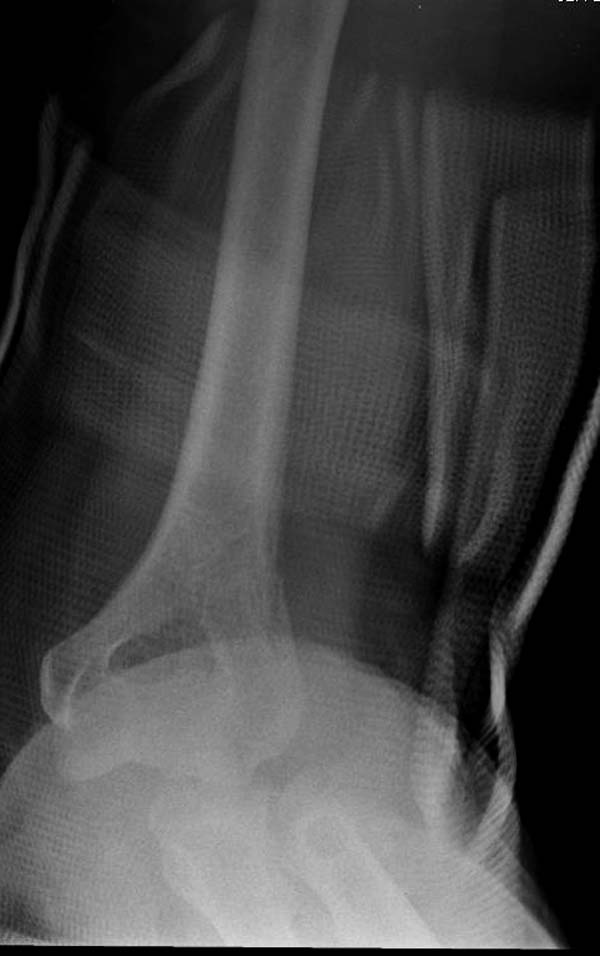

Для примера здесь случай начатый в другом центре, а потом переправленный к нам.

Снимки: 1-2 вывих, 4-5 вторичное смещение в гипсе, реконструкция латеральной связки и капсулы 13-14, повторный вывих после реконструкции, перевод в наш центр; 18-21 временная фиксация, 22-25 трансартикулярная фиксация и нестабильная головка фиксирована спицами, 29-30 амбулаторно, 32-33 после удаления винта и спиц...